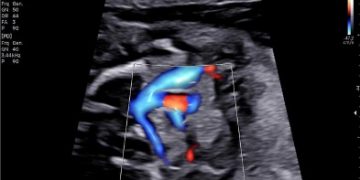

Cari soci, finalmente online le soluzioni dei casi di Maggio!!! Caso 1 Scarica il File Caso 2 [pdf-embedder url="https://www.sieog.it/wp-content/uploads/2022/05/caso-clinico-maggio-2-risposta.pdf" title="caso...